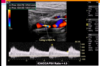

For the following arterial duplex US (DUS) image:

comment on the PRF setting

PRF is set very low

you can tell this based on the velocity range of the color bar (range of 12 cm/s, relatively low setting

recall that PRF value is directly-related to color doppler frequency parameters (and the associated blood velocity)